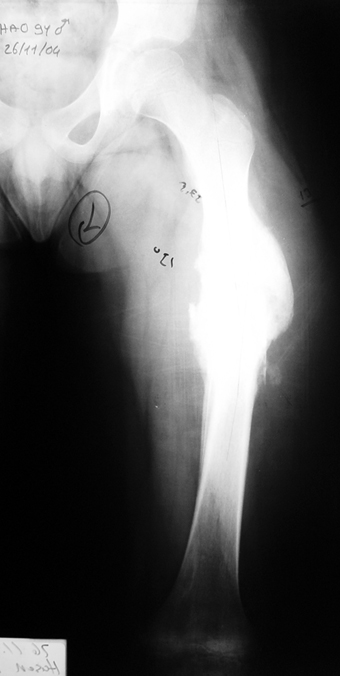

Kronik osteomiyelit, kemik ve yumuşak dokularda nekroza yol açar. Ölü kemik, patojen mikroorganizmalara ev sahipliği yapan bir nidus oluşturur. Konağın savunma sistemleri, mikroorganizmalarla baş etmek için sıklıkla optimal koşullarda değildir. Dolaşım bozukluğu yüzünden enfeksiyon bölgesine antibiyotikler yeterince ulaşamaz. Bu nedenle ölü dokuların ortamdan tamamen uzaklaştırılması gerekir (radikal debridman).

Uygun radikal debridman tüm nekrotik kemik ve yumuşak dokuların çıkartılmasını gerektirir, ve sıklıkla uzuvda instabiliteye neden olur. Kalan kemik ve yumuşak doku defektinin bir şekilde fiksasyonu ve rekonstrüksiyonu gereklidir. İlizarov’un ortaya koyduğu distraksiyon osteogenezi yöntemi, kaynamanın elde edilmesi, deformitenin düzeltilmesi, bacak boy eşitsizliğinin giderilmesi ve segmental defektlerin rekonstrükte edilmesi için başarıyla kullanılmaktadır.